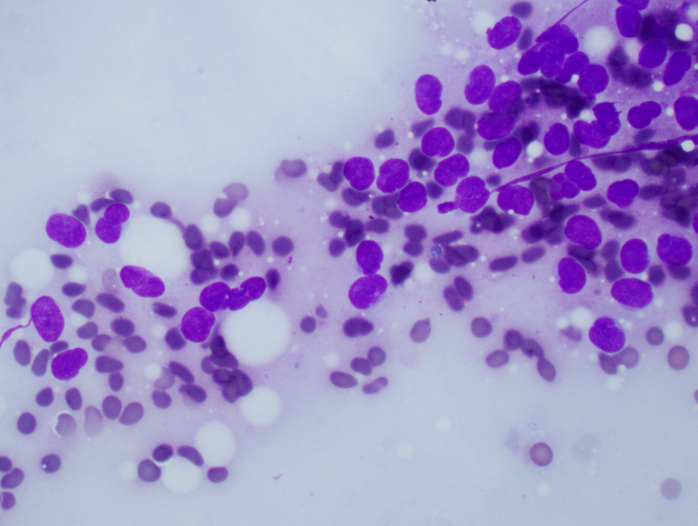

Cytology description

- Uniform small round cells (Diagn Cytopathol 2020;48:1098, Thorac Cancer 2016;7:602)

- Fine chromatin

- Occasional nucleoli

- Scant to indistinct cytoplasm

- Occasional rosette-like structures

Cytology images